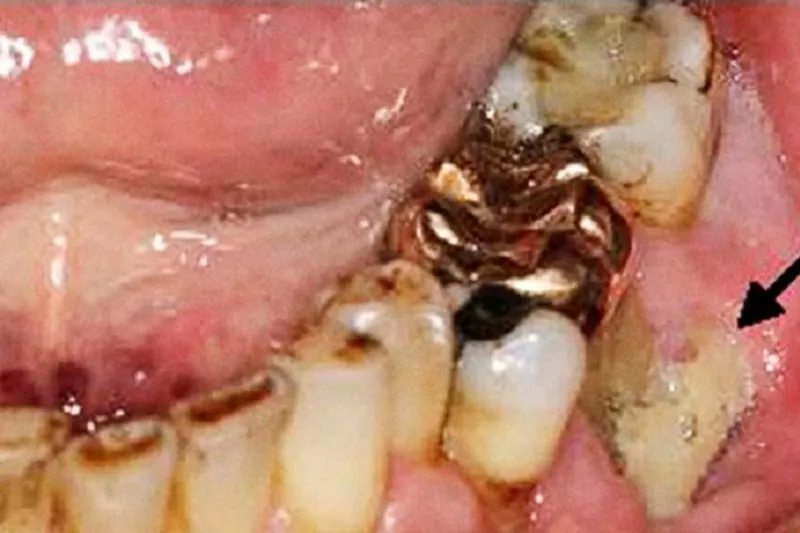

a632 fig. 1